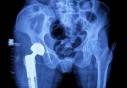

Plusieurs établissements publics de santé de proximité (EPSP) de la wilaya de Sidi Bel-Abbes ont bénéficié de onze équipements de radiologie et d'imagerie, dans le but d’améliorer les prestations assur..